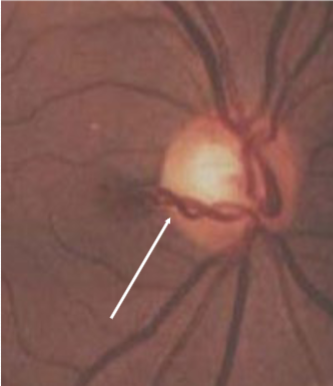

MNF

myelinated retinal nerve fiber (MRNF)

congenital

incidence: 0.3-1%

males = females

oligodendrocytes sheath axons

bilateral in 8% of cases

contiguous w/ ONH in 33% of cases

associations:

myopia

strabismus

amblyopia

appearance:

retinal dense white opacification w/ soft feathered or frayed edges, fine striations following RNF, tend to fan out

isolated patches seen away from ONH in mid-periphery

size varies from ½ DD to several DDs

complications:

rarely macula is involved, but if so, decreased VA)

relative VF defect

must r/o CWS, retinal ischemia, or pale disc

papilledema is partially translucent grayish-white appearance of true edema compared to MNF w/ denser white w/ feathered edge & obscures vessels at disc margin

how do you differentiate between papilledema & MNF?